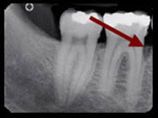

Zahnärztliches Röntgenbild eines Unterkiefers. Ein roter Pfeil zeigt auf den Zwischenraum zwischen zwei Zähnen.